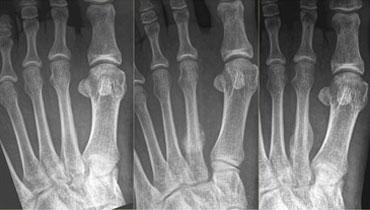

Hình bên trái: nữ bệnh nhân 15 tuổi, không có tiền sử chấn thương.

Đau vùng mu bàn chân phía ngoài khởi phát gần đây khi đi bộ.

X-quang tại thời điểm khám không ghi nhận bất thường.

Theo dõi sau 3 tuần cho thấy gãy hoàn toàn thân xương đoạn xa của xương bàn chân thứ 4 với phản ứng màng xương rõ ràng.

Hình bên trái: nữ bệnh nhân 39 tuổi với triệu chứng đau vùng mu bàn chân khởi phát trong kỳ nghỉ đạp xe.

X-quang tại thời điểm khám bình thường.

Tại các lần theo dõi sau 1 và 3 tháng, có thể quan sát thấy xu hướng lành xương rõ ràng, xác nhận sự hiện diện của gãy xương do stress.